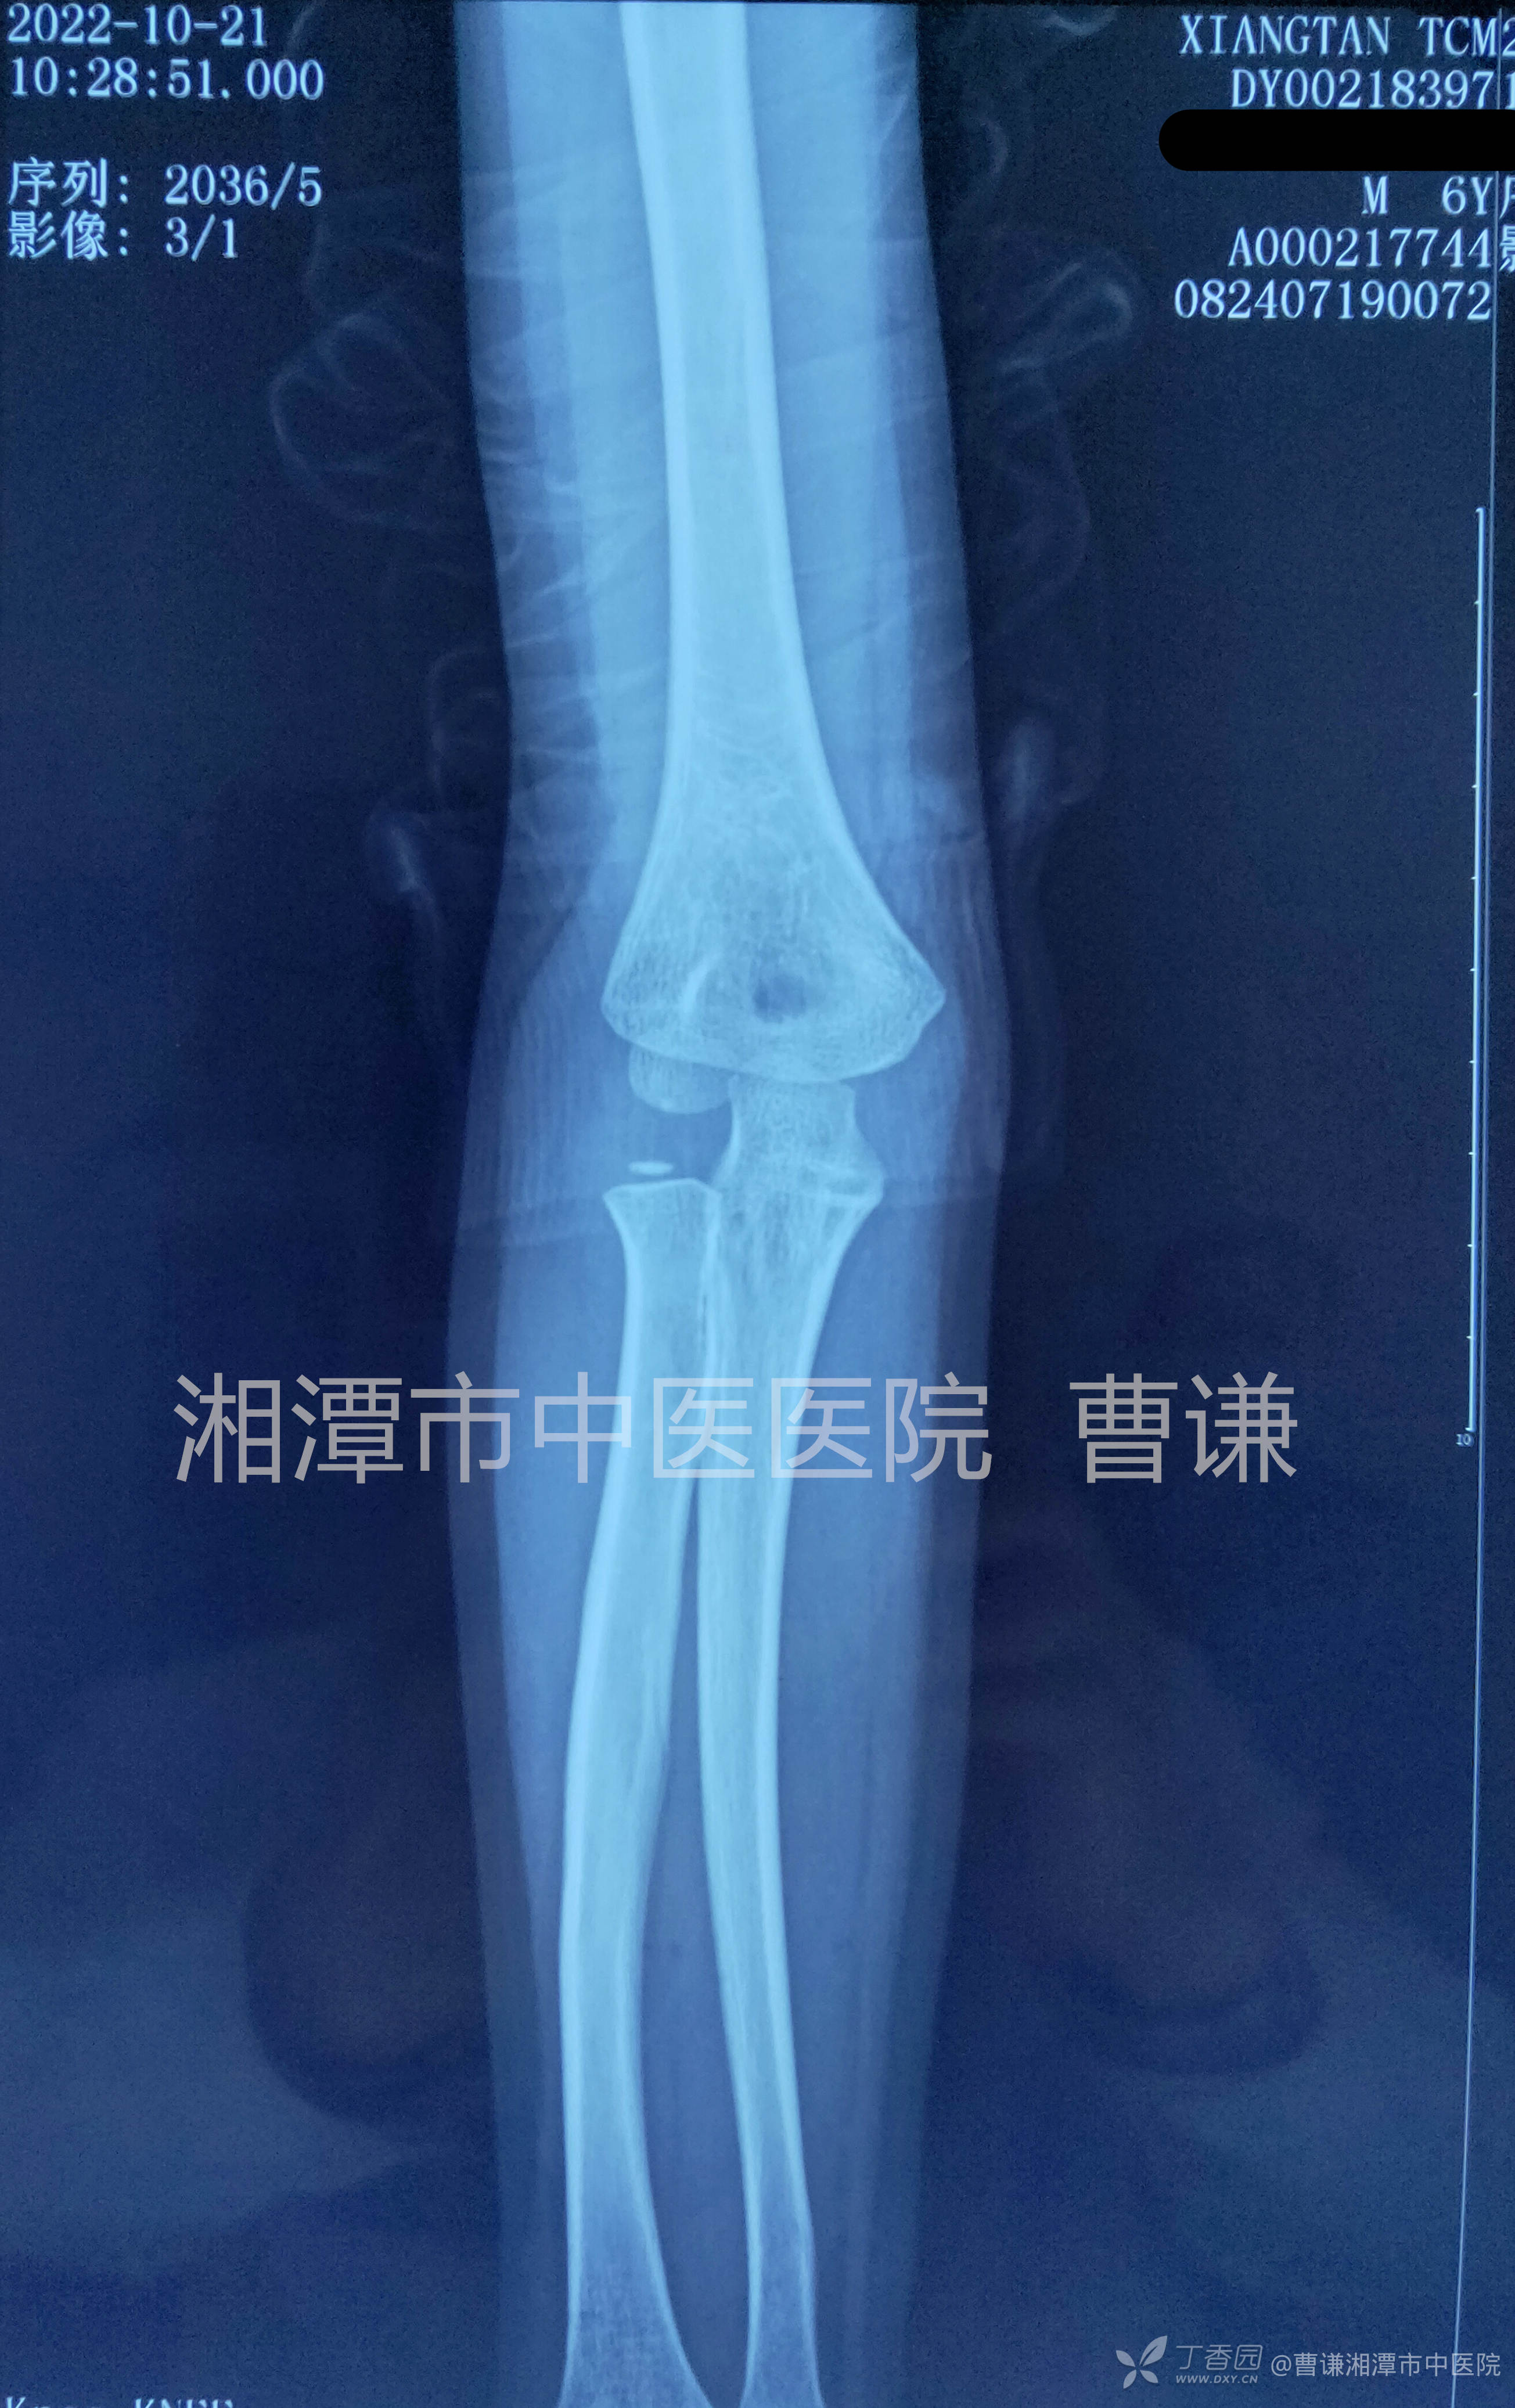

手法复位外固定后复查示尺骨断端对位对线良好,桡骨头与肱骨小头匹配良好。

伤后近一个月复查,见尺骨断端有骨痂生长,虽然放射科老师投照的体位不标准,但还是可以看到桡骨头与肱骨小头匹配良好。

伤后近两个月随访复查示尺骨骨折愈合良好,桡骨头无脱位。

健侧对比片